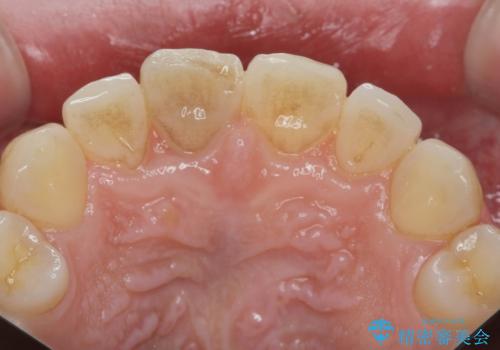

前歯の変色 打撲により失活した前歯の根管・セラミック治療

- 変色してきた前歯の形態回復、色調の改善を求めて来院されました。

X線検査、歯髄(歯の神経)の検査を行ったところ、失活(歯の神経の死んだ状態)であると診断されました。

放置すると変色が進行するだけでなく、根尖病変も形成される恐れが強いことから、根管治療を行ったのちセラミッククラウンによる審美性の改善を計画します。